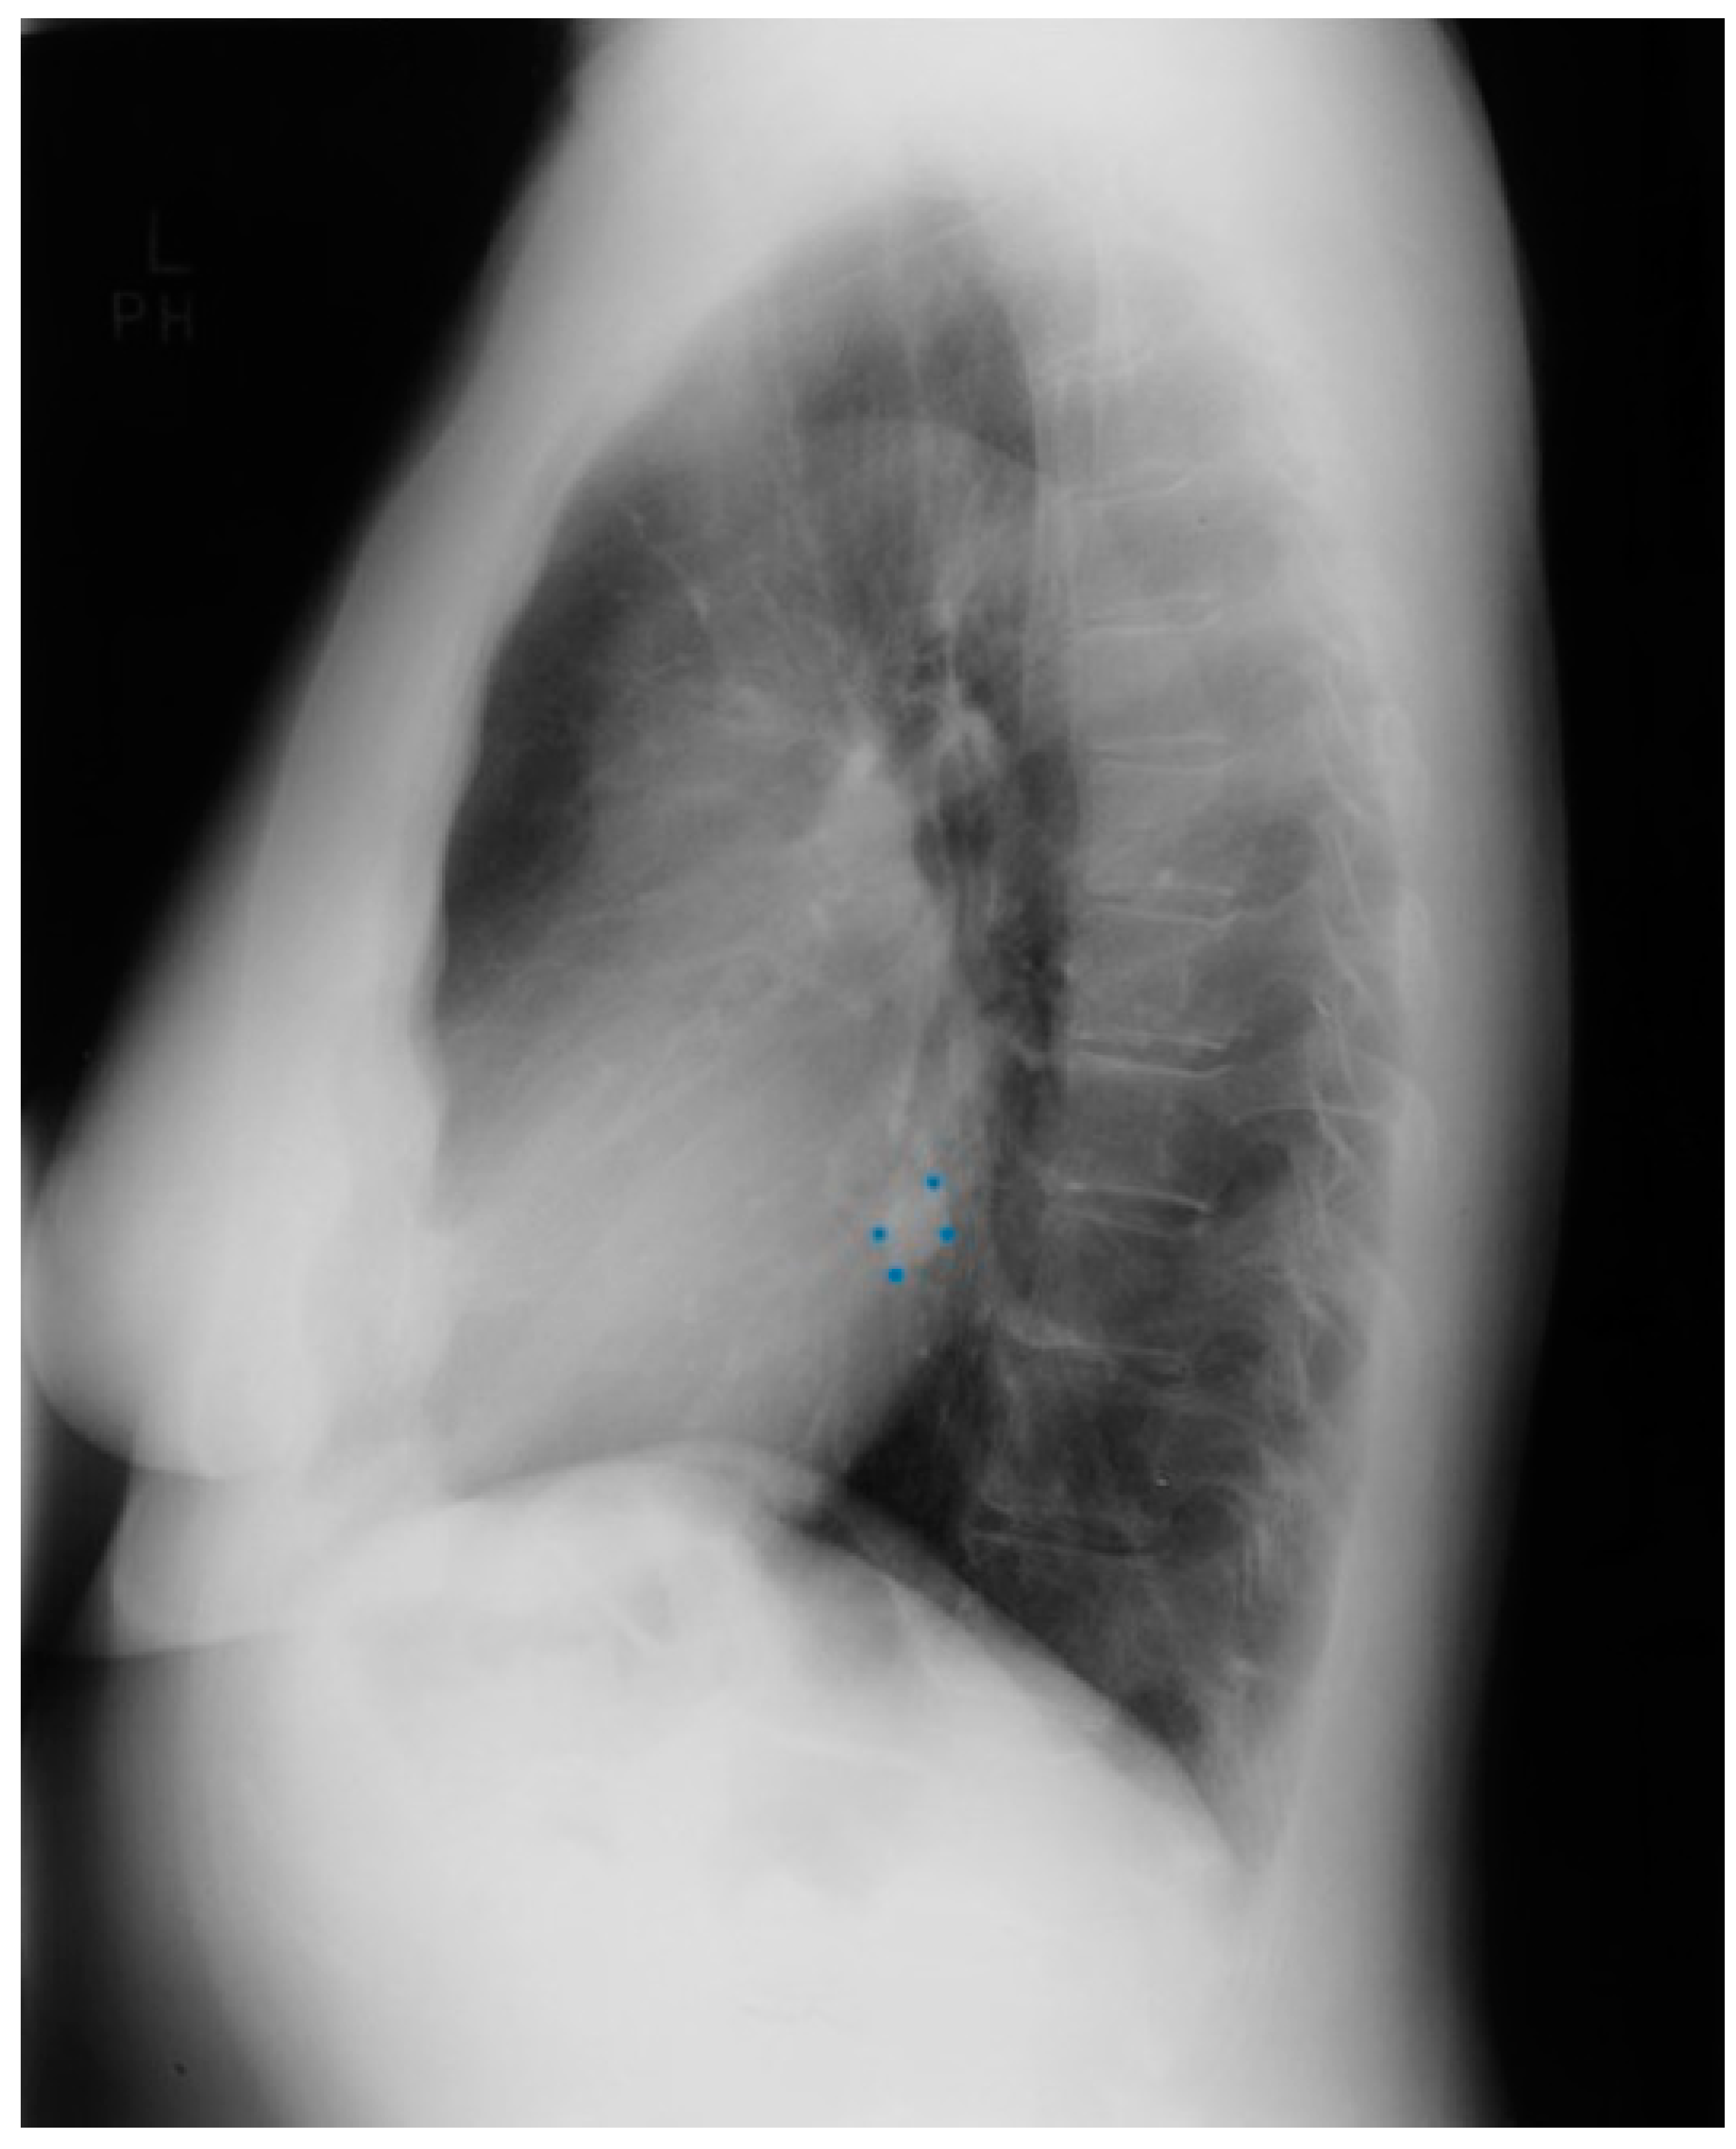

Valvular PS is usually an isolated lesion that occurs in 7–12% of all congenital heart disease cases [7]. The most common form of valvular PS features a dome-shaped pulmonary valve with a narrow central opening but a preserved, mobile valve mechanism. The pulmonary trunk is dilated and the jet from the stenotic valve favors flow to the left pulmonary artery branch. The PS gradient is categorized as mild when peak gradient is <36 mmHg, moderate when 36–64 mmHg, and severe when >64 mmHg. Valvular PS usually presents as an asymptomatic systolic murmur, but severe PS often features intolerance to exercise. Physical examination in a patient with severe PS is usually characterized by an elevated jugular venous pressure with a prominent A wave, an RV heave, and a long, loud systolic flow murmur with wide splitting of S2, if the P2 component is audible. In a study of 87 children aged 4–14 years-of-age with valvular pulmonary stenosis proven by cardiac catheterization, CXR evidence of poststenotic dilatation of the pulmonary trunk (Figure 19) and the left pulmonary artery branch, together with a normal or increased left- sided perihilar pulmonary vascularity, was essential for the diagnosis of valvular pulmonary stenosis [16]. These CXR findings of PS increased with age of the child, but no correlation between these radiographic observations and the severity of the stenosis was found. These same CXR findings are noted in the adult with valvular PS.

Figure 19.

Posteroanterior chest X-ray of severe pulmonary stenosis: this chest X-ray is of a 31-year-old female who presented with worsening exertional dyspnea over the last two years. Her exam revealed elevated jugular venous pressure with prominent A wave. She was noted to have a right ventricular lift with a grade 4/6 systolic ejection murmur best heard at the left upper sternal border. The chest X-ray is well centered and there is a good inspiration. The cardiothoracic ratio is normal. The pulmonary trunk is enlarged (its right border is outlined by blue dots as it passes over the left bronchus). The left pulmonary artery branch that is indicated by two red arrows is also enlarged. Her echocardiogram revealed severe pulmonary valve stenosis with peak gradient 68 mmHg and mild pulmonary valve regurgitation. She subsequently underwent balloon valvuloplasty with reduction of her peak gradient to 24 mmHg. Her symptoms of dyspnea had resolved a few months post-procedure.